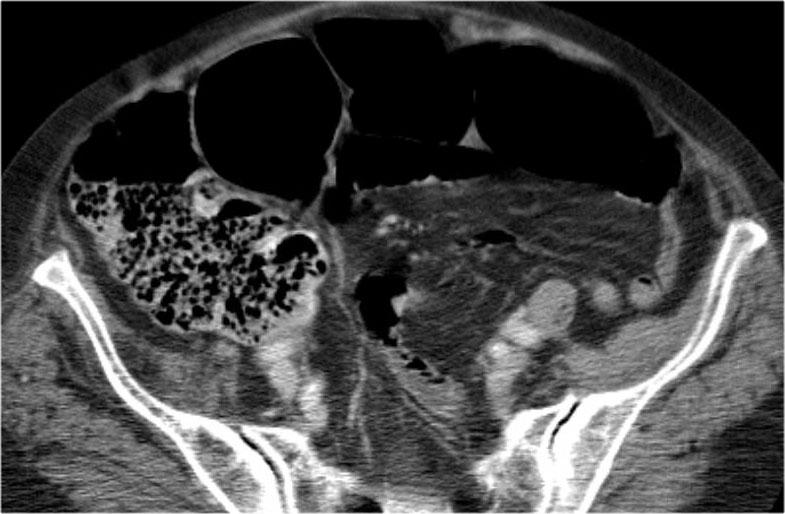

Đây là một bệnh nhân bị tắc ruột non.

Cuộn qua các hình ảnh.

Bạn có thể tìm thấy quai kín và nguyên nhân gây ra nó không?

Hình ảnh CT của tắc ruột non dạng quai kín phụ thuộc vào hai yếu tố:

- chiều dài đoạn ruột tạo thành quai kín

- hướng của quai ruột so với mặt phẳng tạo ảnh

Nếu quai kín ngắn và nằm trong mặt phẳng tạo ảnh, chúng ta sẽ thấy quai ruột hình chữ U hoặc chữ C.

Một hình ảnh quan trọng khác của tắc ruột dạng quai kín là các quai ruột non giãn xếp theo hình nan hoa với các mạch máu mạc treo hội tụ về một điểm trung tâm.

Hình ảnh này hầu như luôn do xoắn ruột non gây ra.

Nếu quai kín dài hơn và định hướng vuông góc với mặt phẳng cắt, chúng ta sẽ thấy một cụm quai ruột như trong ca lâm sàng bên trái.

Đôi khi điều này khó nhận biết chỉ trên các lát cắt ngang và các tái tạo mặt phẳng coronal hoặc sagittal có thể hữu ích.